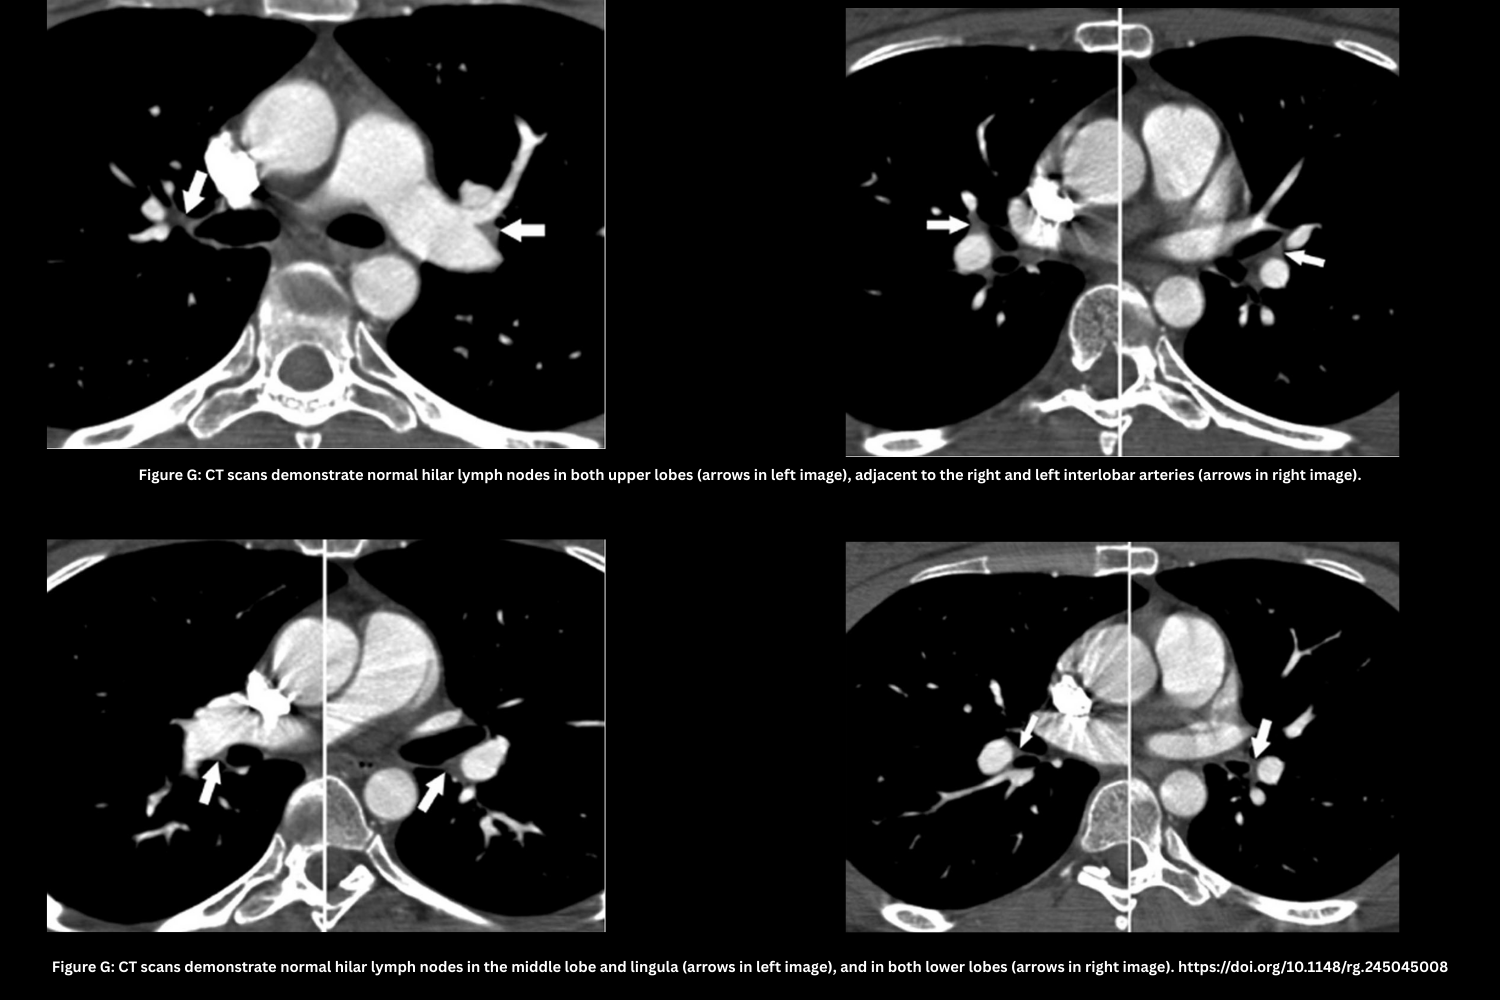

- Partial Volume Averaging Effect in Lymph Nodes (Figure G)

- Hilar lymph nodes overlap the vessel lumen in thick slices.

- Preserved smooth vessel contour distinguishes it from a clot.